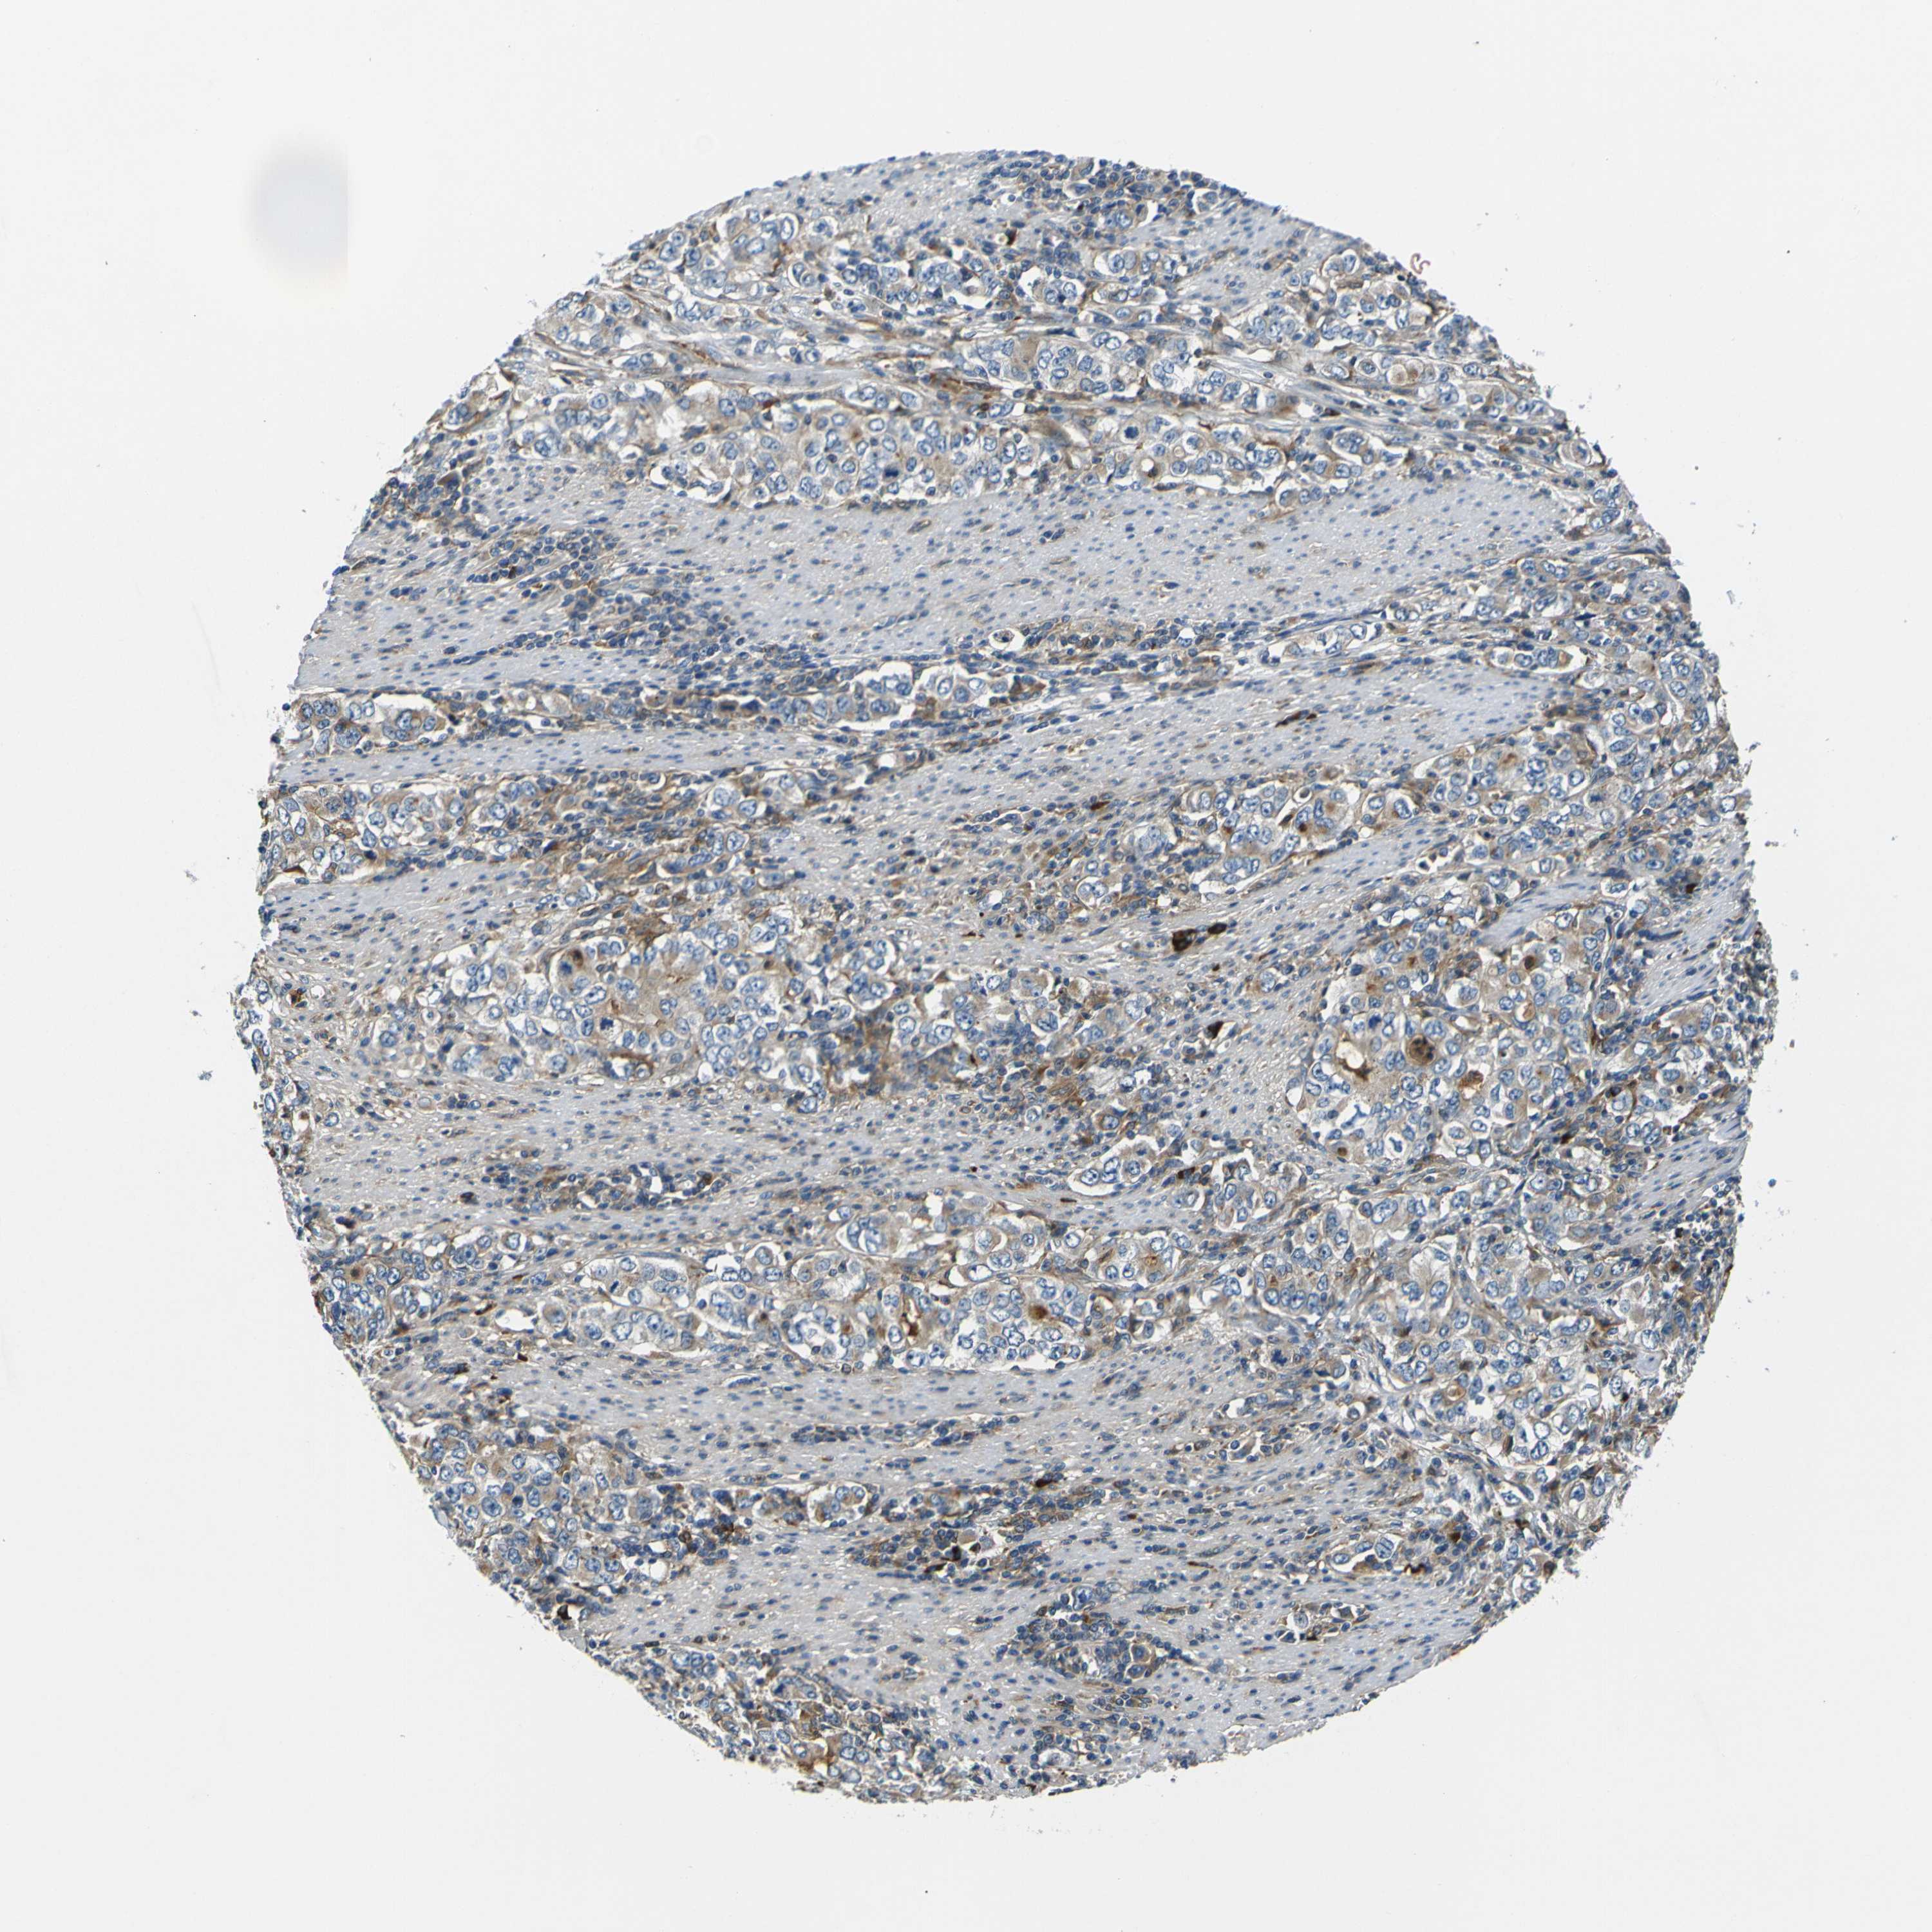

STOMACH CANCER - Protein expressioni

A mouse-over function shows sample information and annotation data. Click on an image to view it in a full screen mode. Samples can be filtered based on level of antibody staining by selecting one or several of the following categories: high, medium, low and not detected. The assay and annotation is described here.

Antibody stainingi

Antibody staining in the annotated cell types in the current human tissue is reported as not detected, low, medium, or high, based on conventional immunohistochemistry profiling in selected tissues. This score is based on the combination of the staining intensity and fraction of stained cells.

Each image is clickable and will lead to virtual microscopy that enables deeper exploration of all samples and also displays staining intensity scores, fraction scores and subcellular localization as well as patient and tissue information for each sample.

Antibody HPA056141

Antibody CAB010225

Staining

High

Medium

Low

Not detected

Intensity

Strong

Moderate

Weak

Negative

Quantity

>75%

75%-25%

<25%

None

Location

Nuclear

Cytoplasmic/membranous

Cytoplasmic/membranous,nuclear

Adenocarcinoma, NOS

Adenocarcinoma, High grade